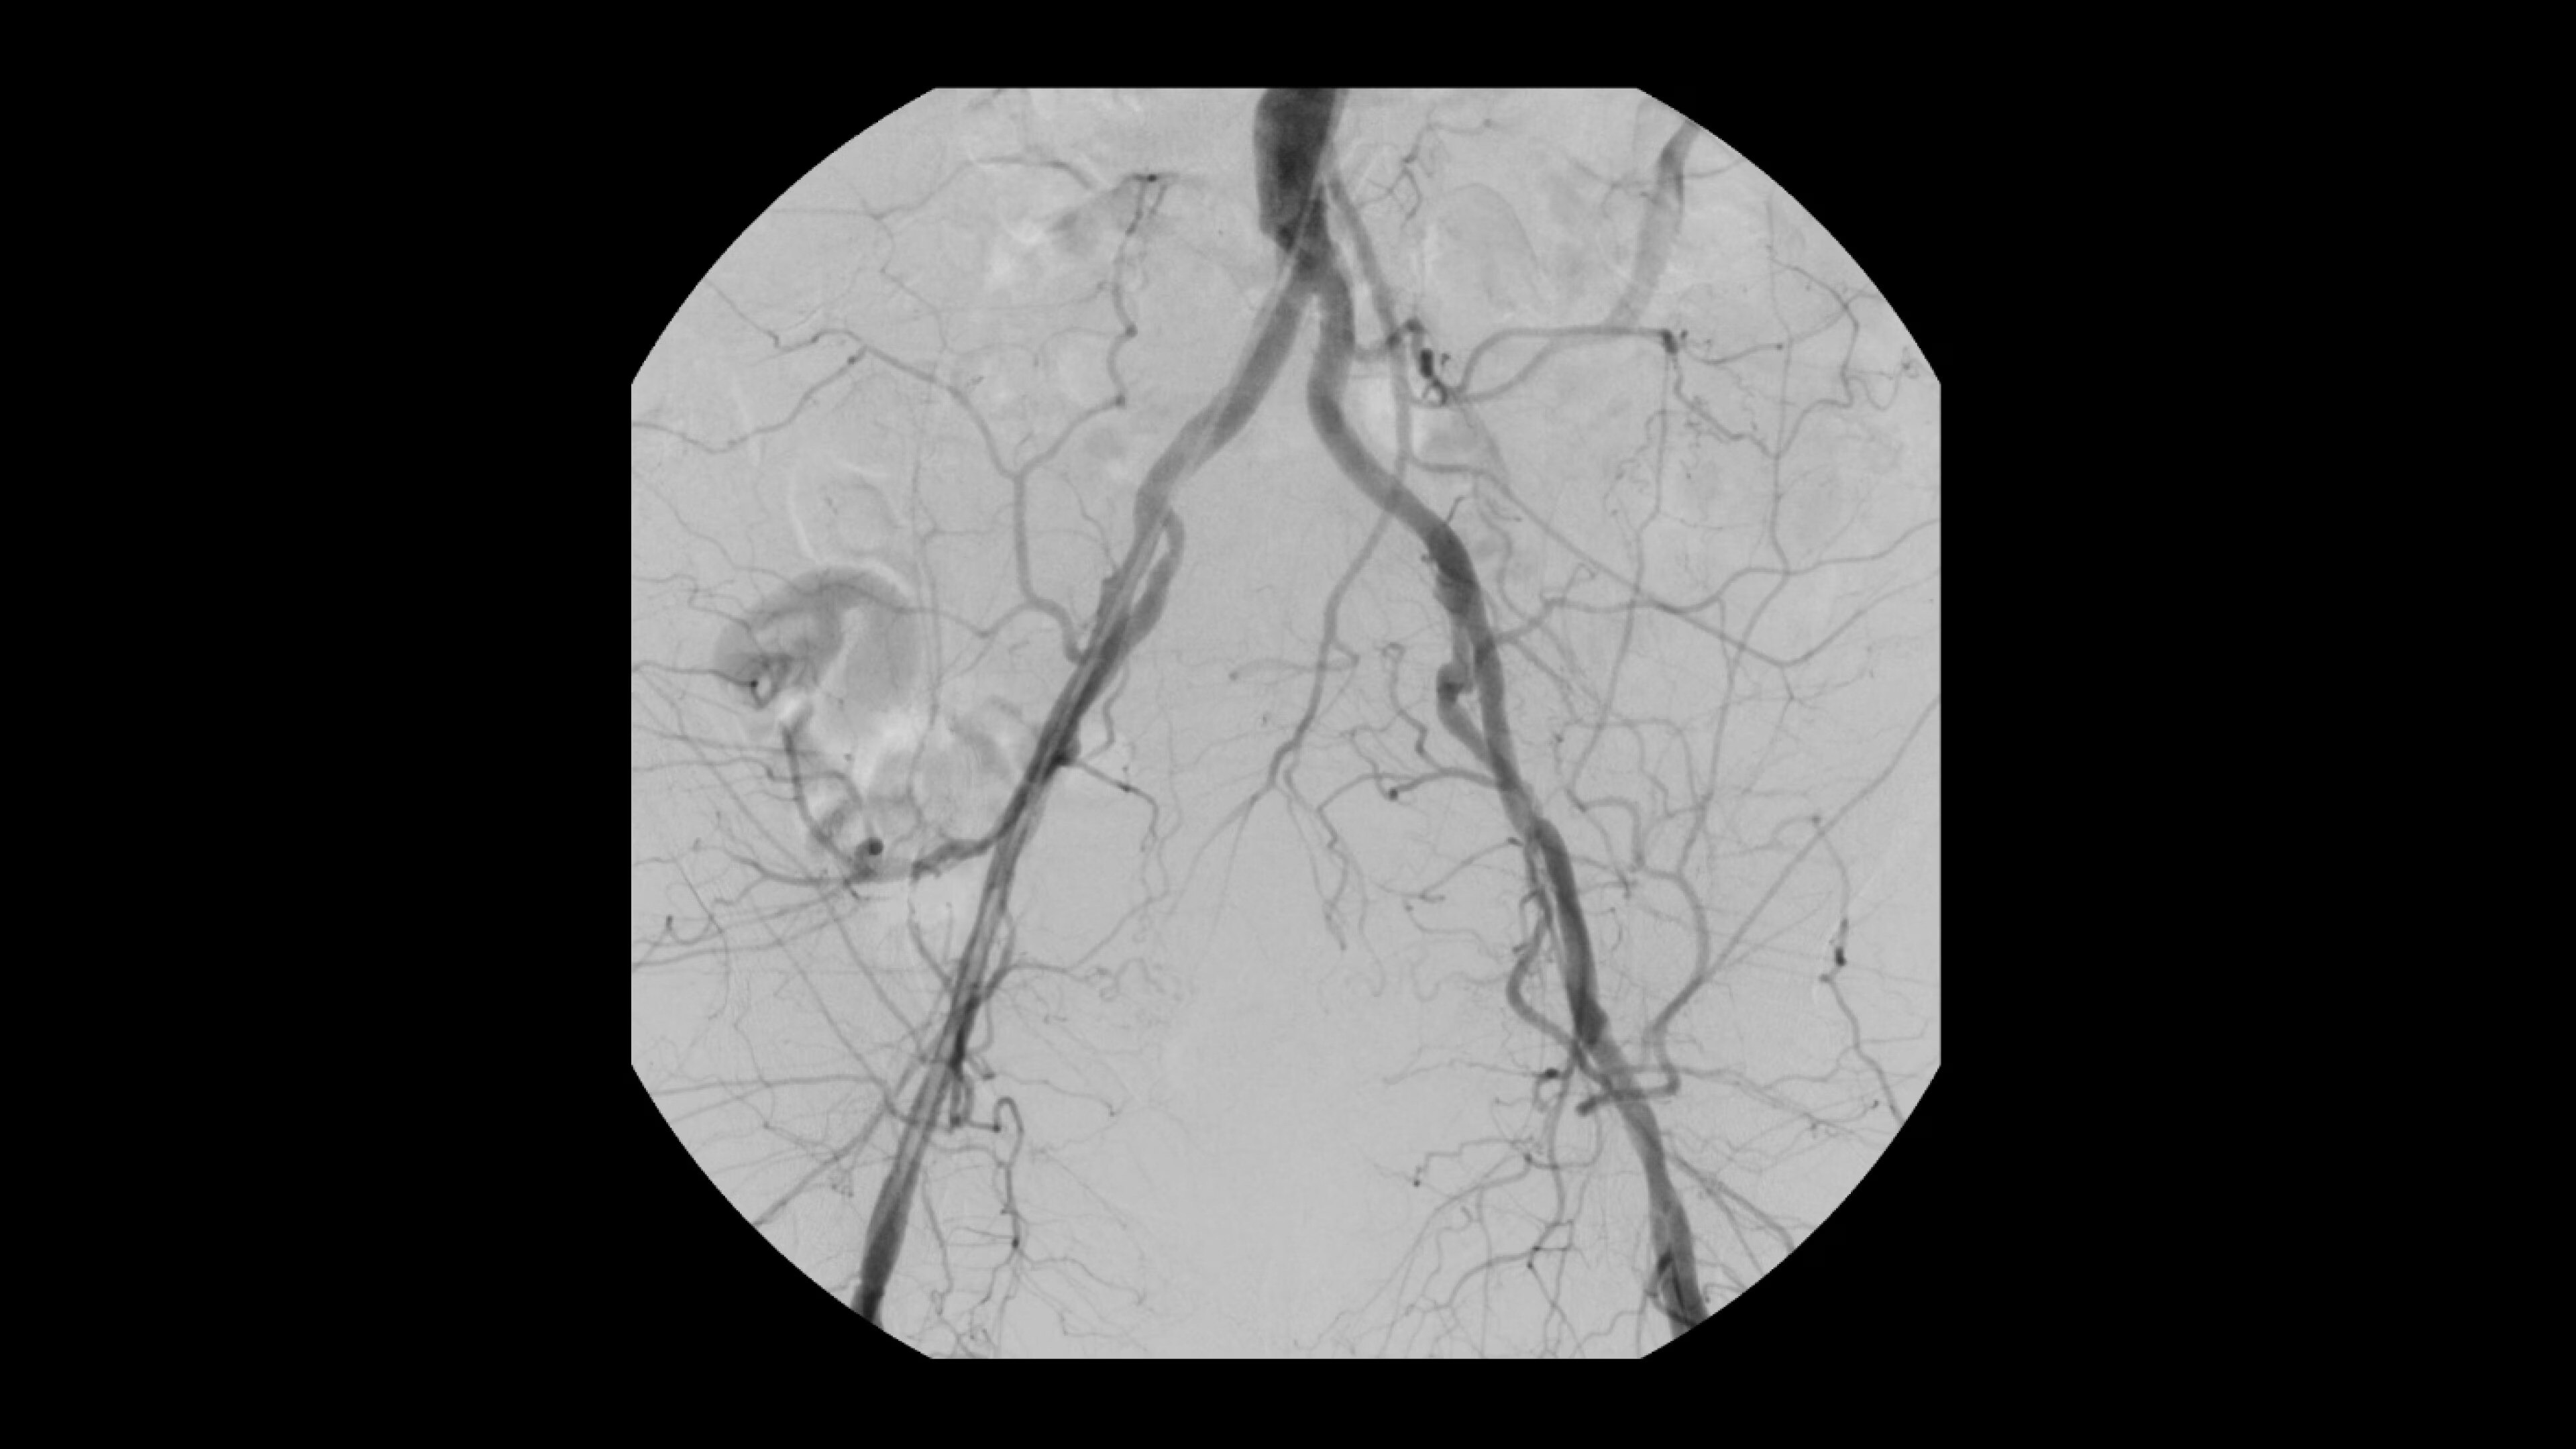

Interventional imaging you need

Interventional procedures require powerful imaging systems. OEC premium

C-arms perform in a variety of procedures such as:

• Prostatic Artery Embolization (PAE)

• Uterine artery embolization

• Pelvic congestion treatments

• Genicular artery embolization

• Venous leak embolization

*Based on GE HealthCare study of OEC 3D imaging results with application of enhanced noise reduction algorithm